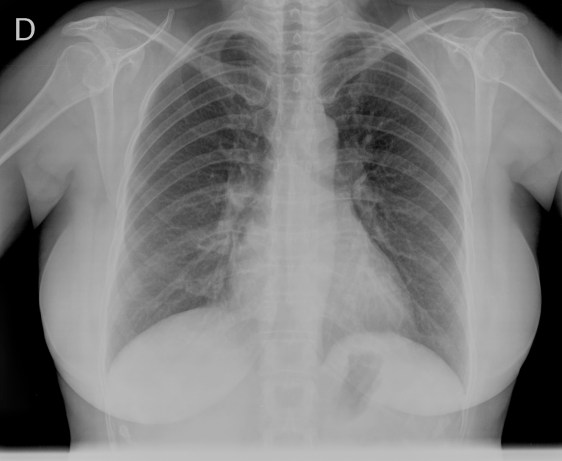

CASO: cáncer de mama. Control anual.

Hallazgos:

- Se observa un aumento de densidad con agrupación broncovascular que produce un borramiento del borde cardicaco derecho; hallazogos compatibles con atelectasia en el lóbulo medio. Véase el TC a continuación: